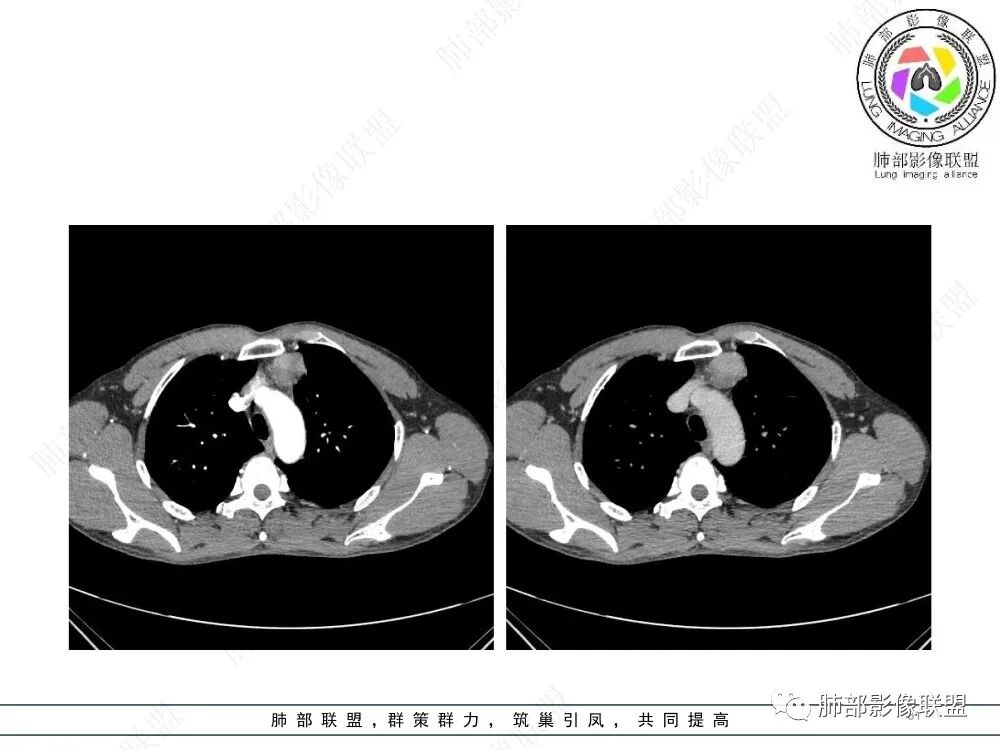

放射小白:男性47岁,前纵隔团块状占位,边界尚清,增强中度强化,内部疑似纤维分隔,常规考虑胸腺瘤可能(A/AB型),鉴别类癌、CD。

Yishion:晨读:纵隔占位,偏侧生长,边界清楚,有浅分叶,强化明显,其内似见纤维分隔,常规考虑胸腺瘤(AB型)。

衡妈🇨🇳:中年男性,前纵隔偏左侧实性占位,密度相对均匀,边缘分叶,周围脂肪结构略模糊,增强后动脉期不均匀强化,有低密度区,纤维分隔显示不清。考虑胸腺瘤B1 B2型。

流心明智:男,47,咳嗽、咳痰1年余。胸部CT:前纵膈偏左类圆形肿块,瘤肺界面清晰光整,纵隔侧部分层面絮状影?平扫密度较均匀,增强后轻度强化,内可见宽带及线样低密度分隔。邻近左上肺受压凹陷。考虑胸腺肿瘤,AB型?胸腺Ca?鉴别淋巴瘤、N源性肿瘤、CD等。

2、影像特点:前纵隔偏左侧软组织影,密度相对均匀,未见明显包膜钙化及实质内钙化,局部边缘浅分叶,周围脂肪间隙密度增高、浑浊,未见侵犯大血管、未见纵隔内淋巴结转移、未见侵犯心包内结构、未见胸膜转移结节、未见肿块沿着纵隔胸膜蔓延,未见胸腔积液。增强后动脉期不均匀强化,未见明显纤维分隔。